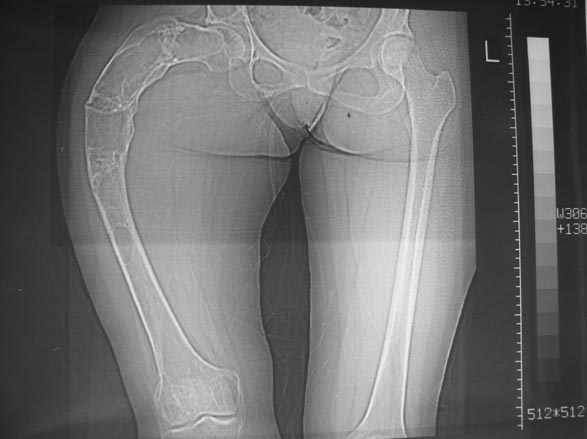

Женщина 28 лет, Больна с 12 летнего возраста, Когда после адекватной травмы получила перелом бедра. На рентгенограммах выявлено какое-то (рентгенограмм и документов нет) изменение бедренной кости, была оперирована, имеется гистологическое заключение - фиброзная дисплазия.дСформировалась деформация бедра. На сегодня - Укорочение 7см. Грубая деформация бедра по типу "пастушьей палки", последний патологический перелом в январе 2004г., консолидировавшийся при консервативном лечении. Имеются грубые изменения и в надвертлужном массиве.-- С уважением, Leonid

Поскольку в данном случае имеется дело с довольно большой деформацией с укорочением, одномоментная её устранение с внутренней фиксацией, чревато с одной стороны неправильной коррекцией, с другой, нейроваскулярными осложнениями.

Моё мнение, что двойная остеотомия бедра с аппаратом Илизарова + Гексаподный механизм, или Тэйлора, В данной ситуации является методом выбора. Я очень извеняюсь за качество прилагаемых снимков, в которых я постарался отразить разницу междe одной и двумя остеотомиями бедра.